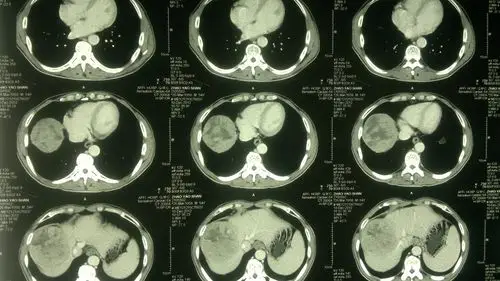

【原创病例】 原发性肝癌,看看手术机会

原发性肝癌的影像表现